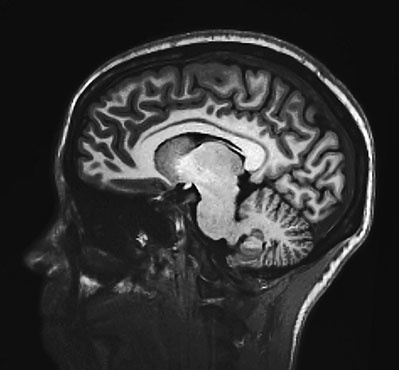

Рис. 6. Поперечное сечение мозга, полученное с помощью МРТ

В последующие годы проводилось много аналогичных исследований, методы которых становились всё более изощренными. На смену анализу оценок за учебу пришли стандартные тесты на интеллектуальные способности – тесты на IQ, как их обычно называют. Гальтон оценивал величину головы, измеряя ее длину, ширину и высоту, а затем перемножая полученные числа. Другие исследователи измеряли окружность головы при помощи ленты-сантиметра. Самые отважные предпочитали извлекать мозг умерших и взвешивать его. Сейчас все эти методы кажутся примитивными, ведь в наше время ученые могут видеть живой мозг прямо сквозь череп, используя магнитно-резонансную томографию (МРТ). Эта потрясающая технология дает возможность получать изображения поперечных сечений мозга на заданной глубине (рис. 6).

В сущности, МРТ как бы виртуально рассекает голову на ломти и создает двухмерное (2D-) изображение каждого из них. Получается целый набор 2D-картинок, и по нему специалисты воссоздают форму всего мозга в трех измерениях, получая уже 3D-изображение. А затем можно весьма точно вычислить объем мозга. Благодаря МРТ стало гораздо легче проводить работы по сопоставлению IQ и объема мозга. За прошедшие два десятка лет осуществлено множество таких исследований. Ученые пришли к единому мнению: в среднем у людей с более крупным мозгом IQ выше.